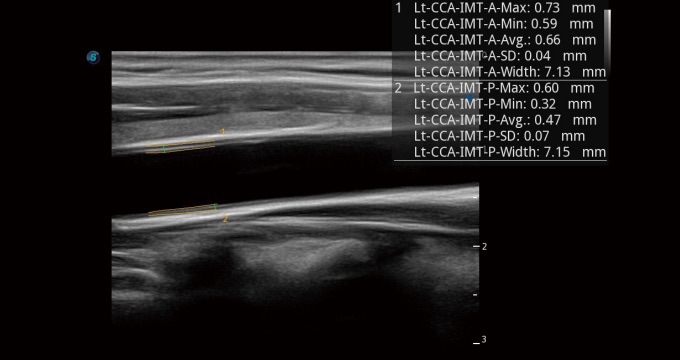

• Auto IMT

Auto IMT es una herramienta inteligente para analizar el riesgo potencial de enfermedad cardiovascular en un paciente. Al hacer clic en un botón, puede medir tanto el grosor de la íntima-media anterior como posterior de la carótida común. Este sencillo procedimiento mejora la productividad del examen, además de agregar valor de diagnóstico al examen.

Arteria carótida